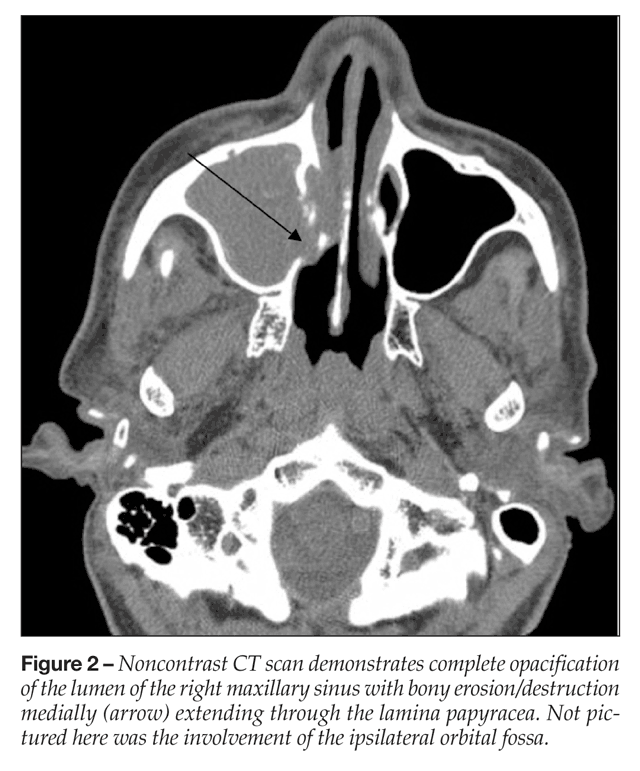

Acute Invasive Fungal Rhinosinusitis A Comprehensive Update Of Ct Findings And Design Of An Effective Diagnostic Imaging Model American Journal Of Neuroradiology